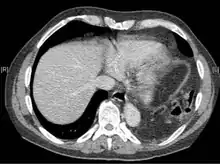

A CT scan has an increased accuracy of diagnosis over X-ray,[7] but no specific findings on a CT scan exist to establish a diagnosis.[9] The free edge of a ruptured diaphragm may curl and become perpendicular to the chest wall, a sign known as a dangling diaphragm. A herniated organ may constrict at the location of a rupture, a sign known as the collar sign. If the liver herniates through a rupture on the right side, it may produce two signs known as the hump and band signs. The hump sign is a form of the collar sign on the right. The band sign is a bright line that intersects the liver. it is believed to result due to the ruptured diaphragm compressing.[13] Although CT scanning increases chances that diaphragmatic rupture will be diagnosed before surgery, the rate of diagnosis before surgery is still only 31–43.5%.[7] Another diagnostic method is laparotomy, but this misses diaphragmatic ruptures up to 15% of the time.[4] Often diaphragmatic injury is discovered during a laparotomy that was undertaken because of another abdominal injury.[4] Because laparotomies are more common in those with penetrating trauma than compared to those who experienced a blunt force injury, diaphragmatic rupture is found more often in these people.[14] Thoracoscopy is more reliable in detecting diaphragmatic tears than laparotomy and is especially useful when chronic diaphragmatic hernia is suspected.[4]